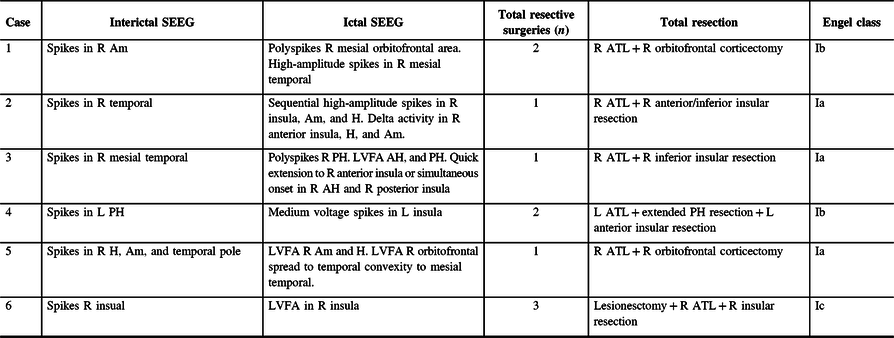

Case 2: Thirty-two-year-old, right-hand dominant male with a history of reflex epilepsy triggered by eating for 5 years. The patient sustained somatosensory seizures with oral automatisms, left head and eye deviation, and postictal right-hand nose wiping. Neuropsychological testing was normal with left language lateralization. MRI revealed hippocampal sulcus remnant cysts on the right. These were considered incidental findings with no abnormal changes in hippocampal volume or signal. PET scan was normal. Scalp EEG showed right temporal seizures extending to the suprasylvian region. The patient was investigated with SEEG, and seven seizures with simultaneous onset in the right hippocampus and inferior insula were recorded (Figure 2). The patient was offered a right ATL with partial resection of the insular cortex. The latter was performed with the aid of neuronavigation, accessing the insula transpially and resecting the tissue that overlapped the active contacts of the depth electrodes involved (Figures 1B, 3A–J and 4A and B). Patient has remained seizure-free since surgery, 1.3 years ago.

Figure 2: Case 2. Ictal Stereo-EEG (Referential montage): all the seizures recorded were electrographically stereotyped and preceding the clinical onset. Simultaneous onset with high voltage spikes over right anterior insula, amygdala, and anterior hippocampus (onset shown with yellow arrowheads), followed by sequential spikes spreading to adjacent electrodes. Subsequently, ictal activity involved nearly all electrodes and ended abruptly (ending not included in the image).